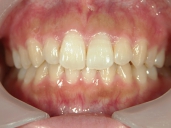

矯正歯科 治療前 正面

矯正歯科 治療後 正面